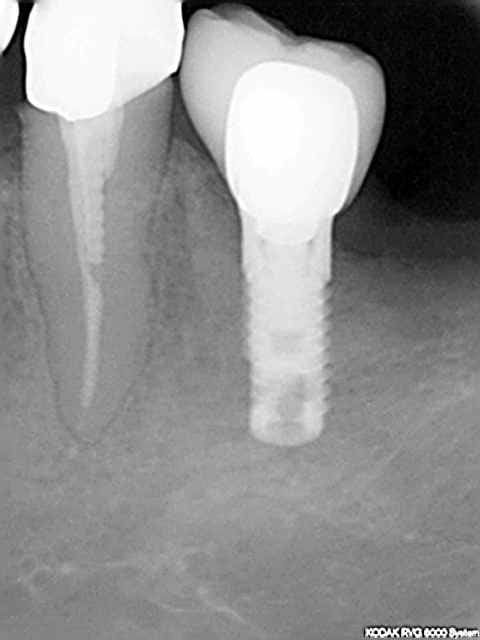

suite à ce cas que j'avais posté

hier fait une rvg de controle sur deux implants posés en 2007 (serf evl+) et en mésial on distingue nettement que l'os s'est formé sur le col lisse...

j'ai constaté aussi un peu la même chose sur ce cas (et sur d'autres)

je précise que l'incidence est la même entre les 2 clichés.

c'est plutôt rassurant ces reconstructions osseuses péri-implantaires.